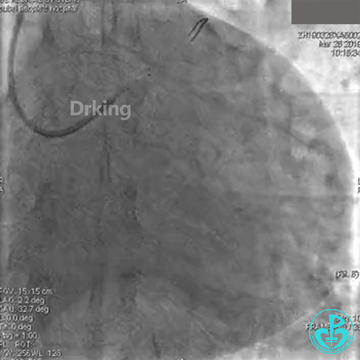

此时反复看造影图,发现LCX有一支高位的小的OM,预想是否可以把导丝送至高位OM远段,再用双腔微导管辅助支撑下将另一根导丝通过严重扭曲处送至LCX远段呢?

以下是导丝成功通过严重扭曲病变的图:

把Sion导丝送至高位OM的远段,在双腔微导管的辅助支撑下,把BMW导丝通过LCX扭曲及病变处顺利送至远段,撤出双腔微导管,2.0×20mm球囊对病变处PTCA后狭窄减轻,于病变处植入2.75×23mm支架一枚,后分别用2.75×12mm、3.0×12mm球囊对支架内后扩,复查造影原病变处狭窄消失,TIMI血流三级。